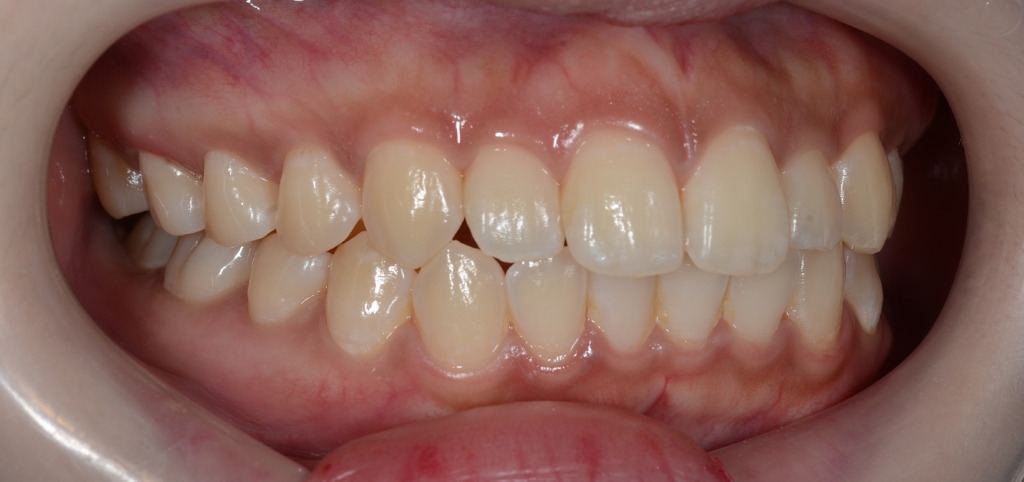

左側が矯正治療前、右側が矯正治療後

オトガイ部にあった梅干し状のシワがほぼ無くなったことが分かります。

矯正後は口元がとてもスッキリしたことが見て取れると思います。